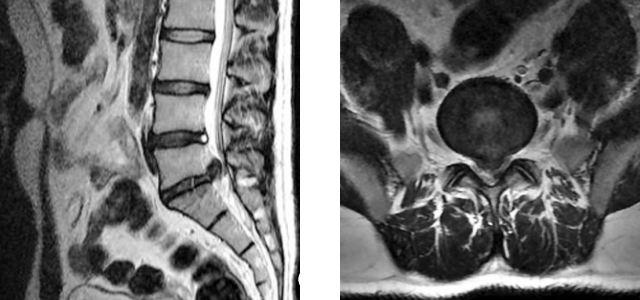

Jane had gone to Susan George for her physical therapy for four weeks and is no longer experiencing pain at this point. She has not had to take any pain medication in the previous week, and has returned to training for her excitedly anticipated Race for the Cure walk. Ms. George encourages her to continue to be active after the race is over as this is the best way of preventing reinjury, and the exercise will really benefit her in other ways. Jane returns to Dr. Kim and informs her that she had enrolled in a research study that the physical therapist introduced to her. As part of this study, Jane had new MRI imaging done and she shares them with Dr. Kim.

MRI shows healing

Dr. Kahn tells Jane that the images show what Jane feels, that all is now well with her.

Imaging is not indicated in acute lower back pain or sciatica. One indication for MRIs and x-rays is sciatica that does not resolve in six weeks. An MRI becomes indicated for Jane when the condition suddenly worsened following the misstep on the stairs. Imaging after symptoms subside is contraindicated. It was done in this case only because Jane was in a research study which included an MRI as part of the study. The physical therapist told her of a study that matched her symptoms, and Jane decided she would like to enroll.